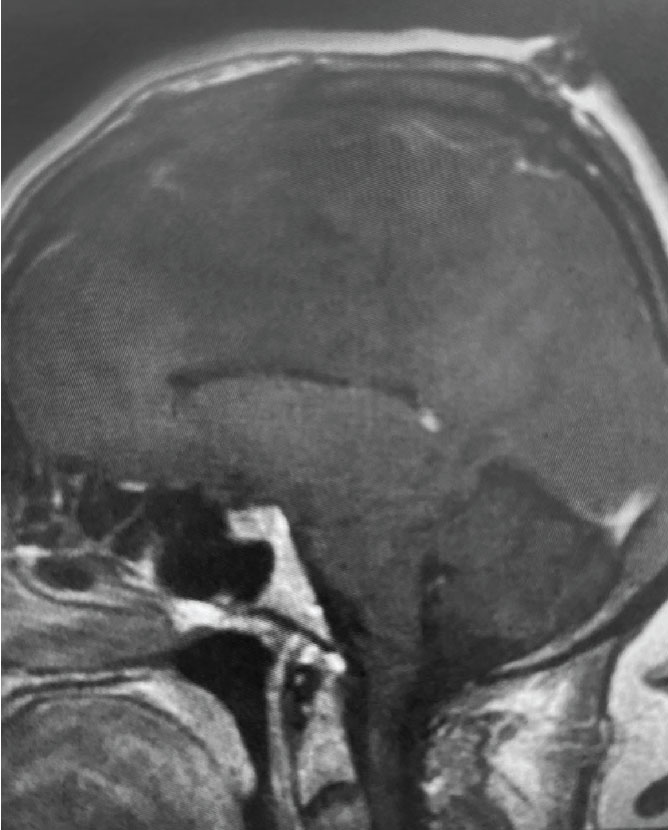

Fig 1. B) Pre-operative, sagittal post-contrast MRI.

This is a 55 year old right-handed woman who was having progressive balance problems. MRI with and without contrast demonstrated a 7 cm partly cystic meningioma involving the left frontal convexity and falx, and encasing the superior sagittal sinus. There was also tumor involvement of part of the convexity skull.

Meningiomas that involve the superior sagittal sinus: Sometimes convexity or falx meningiomas will grow into the superior sagittal sinus. Sometimes the sinus can become completely occluded. Usually this occurs over many years, and as such, the brain has time to develop venous collaterals. So, while in a normal person, sudden occlusion of the superior sagittal sinus could lead to venous infarction or death, the very gradual occlusion that can be seen with meningiomas, does not lead to these problems. Also, if the sinus is filled with tumor and completely occluded, it can usually be safely removed at that segment.

Convexity and Falx Meningiomas: While meningiomas can involve either the convexity or the falx alone, it is possible for such tumors to involve both structures. In this case, vascular supply to the tumor can originate from both dural sources. When meningiomas involve the convexity dura, the dura is often excised and replaced with a duraplasty (an artificial dural replacement). When tumors involve the falx, the falx itself is usually not removed in entirety.